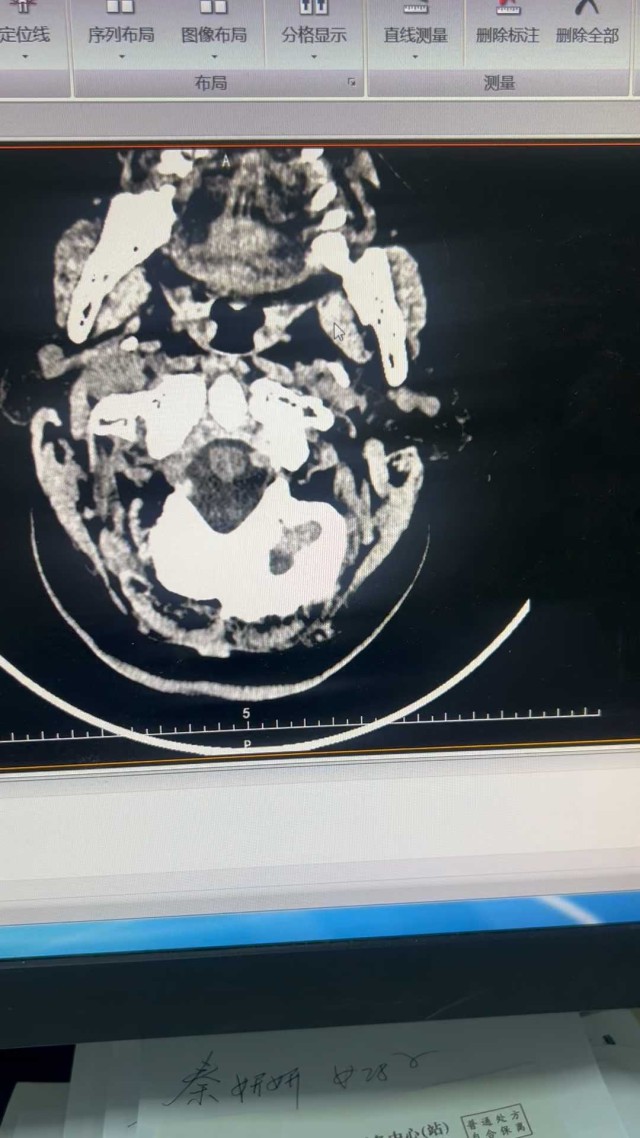

白某某,女性,73岁,2024年01月09日入院。主诉:进展性双下肢无力15天现病史:15天前(12月26日7:00)无明显诱因突发双下肢无力,可缓慢行走,(12月26日9:00)渐进行性加重,双下肢抬离床面困难,不能行走,伴双下肢感觉障碍,小便困难及大便失禁,持续性,无头痛、眩晕、恶心、呕吐,无意识丧失、肢体抽搐、口吐白沫、双眼凝视,偶有口角流涎,无言语含糊、饮水呛咳、吞咽困难。立即就诊于当地县人民医院,因起病急,症状重,病情进展快,双下肢感觉障碍,尿便障碍,短时间内诊断困难,当天转诊于某大学附属医院神经外科,按双下肢无力待查:胸髓缺血诊治后好转,双下肢较前有力,可借助外物缓慢挪步,行走不稳

coverplay

病例 · 319 浏览 · 4 讨论